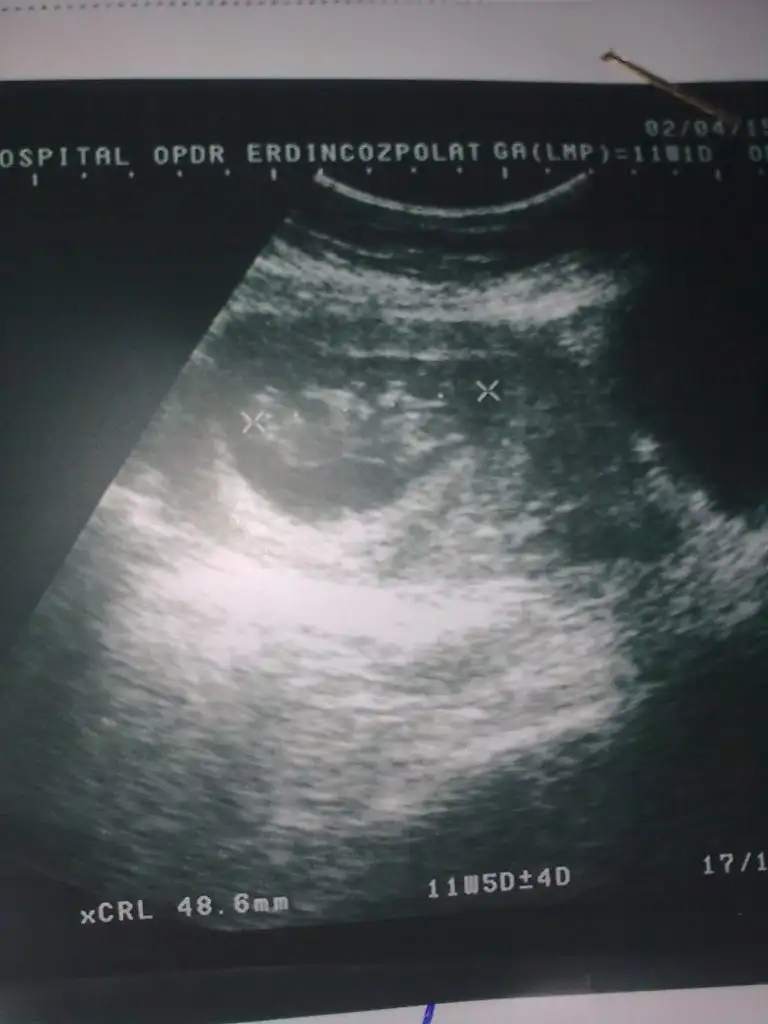

Kızlar çok yoğunum yazamıyorum kusura bakmayın. Hamile olan goamıydı hayırlı olsun Rabbim gönlüne göre versin inşallah. Kese fotosu atan eyhammıydı bebeği keseye göre erkek kese içinde sağda bebek çünkü. Bu dr remzi teorisiymiş. Test atan arkadaş inan testlerden anlamıyorum ama testte hata daha yüksek bence ağrı ve ateşe göre yaptıysan daha mantıklı yapmışsın. Asosyalci bebeğin foto koy bakalım belki biz yorum yaparız. Şuan okadar yoğunum isimler vs karıştı ama neyi kime yazdığımı anlar herkes inşallah

atıyorum hadi inş.